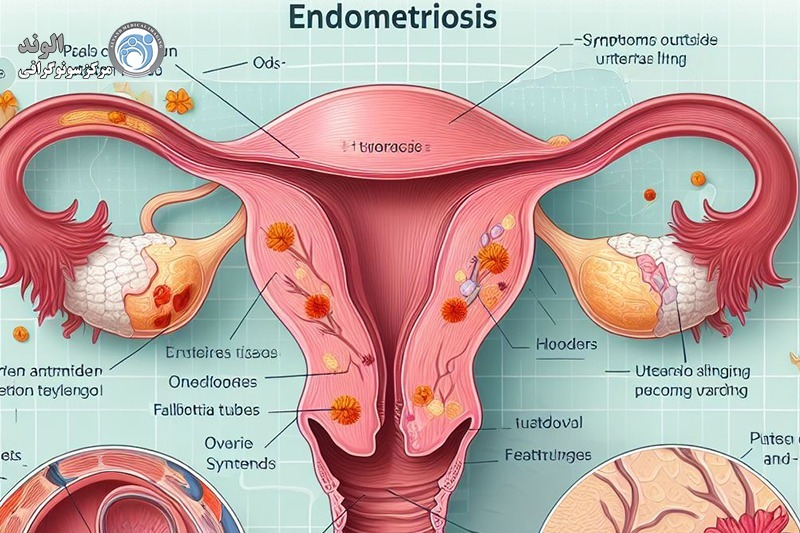

این بیماری زمانی اتفاق میافتد که بافت مشابه با بافت داخلی رحم (آندومتر) در جایی خارج از رحم رشد میکند، معمولاً در تخمدانها، لولههای فالوپ یا سایر اندامهای لگنی. علائم آندومتریوز میتواند شامل دردهای شدید قاعدگی، درد در حین رابطه جنسی، مشکلات باروری و خونریزی غیر طبیعی باشد. با این حال، بسیاری از زنان مبتلا به آندومتریوز ممکن است بدون علائم جدی یا فقط علائم خفیف داشته باشند، که این ممکن است تشخیص بیماری را دشوار کند.

اندومتریوز یک بیماری زنان است که در آن بافتی مشابه به بافت داخلی رحم (اندومتر) در خارج از رحم رشد میکند. این بیماری میتواند به شدت دردناک باشد و مشکلاتی چون ناباروری، دردهای مزمن لگنی، و اختلالات قاعدگی را ایجاد کند. تشخیص زودهنگام اندومتریوز اهمیت زیادی دارد زیرا میتواند به مدیریت مؤثرتر علائم و بهبود کیفیت زندگی بیماران کمک کند. یکی از روشهای رایج و غیرتهاجمی برای تشخیص اندومتریوز استفاده از سونوگرافی است که به ویژه در شناسایی برخی از ویژگیهای این بیماری بسیار مؤثر است.

به ندرت، لکه های اندومتریوز در سایر نقاط بدن رخ می دهد. این می تواند باعث ایجاد دردهای غیرعادی در قسمت هایی از بدن شود که همزمان با دردهای پریود رخ می دهد.اندومتریوز باعث می شوددر طول سالیان متمادی تئوری های مختلفی برای علت آندومتریوز وجود داشته است. پوشش داخلی رحم (رحم) آندومتر نامیده می شود. یک نظریه این بود که برخی از سلول های آندومتر به خارج از رحم وارد ناحیه لگن می شوند. وقتی پریود میشوید، با ریختن به سمت عقب در امتداد لولههای فالوپ به آنجا میرسند.لکه های اندومتریوز تمایل دارند "چسبنده" باشند و ممکن است اندام ها را به یکدیگر بپیوندند. اصطلاح پزشکی برای این چسبندگی است. برای مثال، مثانه یا روده ممکن است به رحم «بچسبد». تکه های بزرگ آندومتریوز ممکن است به کیست هایی تبدیل شوند که هر ماه هنگام پریود شدن شما خونریزی می کنند. کیست ها می توانند با خون تیره پر شوند و به عنوان کیست های شکلاتی شناخته می شوند.

تشکیل کیستها: در برخی موارد، اندومتریوز میتواند منجر به تشکیل کیستهایی به نام "اندومتریوما" در تخمدانها شود که ممکن است دردناک باشند و حتی در صورت عدم درمان، به جراحی نیاز پیدا کند.

یکی از ویژگیهای بارز اندومتریوز ایجاد کیستهایی به نام اندومتریوما (یا "کیست شکلاتی") است که در تخمدانها یافت میشود. این کیستها از خون و بافت مشابه اندومتر تشکیل شدهاند. سونوگرافی میتواند این کیستها را به وضوح شناسایی کند. در تصاویر سونوگرافی، کیستهای اندومتریوز معمولاً به صورت تودههای گرد و یا بیضی با محتوای داخلی خاص دیده میشوند که ممکن است به رنگ تیرهتر از سایر بافتها ظاهر شوند.

مشاهده چسبندگیهای لگنی

یکی از ویژگیهای شایع اندومتریوز، چسبندگیهای لگنی است که ممکن است بین رحم، تخمدانها و سایر اندامهای لگنی ایجاد شود. سونوگرافی قادر است تغییرات آناتومیک در ساختارهای لگنی را شناسایی کند که ممکن است ناشی از چسبندگیها و در نتیجه اندومتریوز باشد. با این حال، تشخیص دقیق چسبندگیها معمولاً به ترکیب سونوگرافی با روشهای دیگر نیاز دارد.

شناسایی تغییرات در رحم و تخمدانها

در برخی از موارد، اندومتریوز میتواند موجب تغییرات در بافت رحم یا تخمدانها شود. سونوگرافی میتواند در تشخیص تومورهای غیرمعمول یا ضخیم شدن دیواره رحم (که ممکن است ناشی از اندومتریوز باشد) کمک کند. همچنین این روش میتواند به شناسایی و ارزیابی وضعیت تخمدانها در بیمارانی که دارای اندومتریوز هستند، کمک کند.

شناسایی ضایعات در رودهها و دیگر ساختارهای لگنی

در موارد پیشرفتهتر اندومتریوز، بافتهای اندومتریوزی ممکن است به رودهها، مثانه یا دیگر ساختارهای لگنی گسترش یابند. در این موارد، سونوگرافی میتواند به شناسایی ضایعات و گسترش بیماری کمک کند، اما معمولاً برای ارزیابی دقیقتر نیاز به استفاده از روشهای تصویربرداری دیگر مثل MRI وجود دارد.